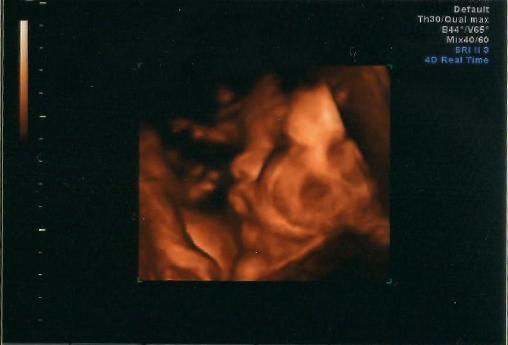

Dávám sem teda ten páteční obrázek toho našeho cvaldy, jsem zvědavá, jaká pak bude skutečnost :)

Evka - jééé, ten je fajný

Evi, miminko je nádherné, má krásně buclaté tvářičky, tak jsem fakt zvědavá, jak to bude odpovídat realitě, jestli si bude podobný. :-)